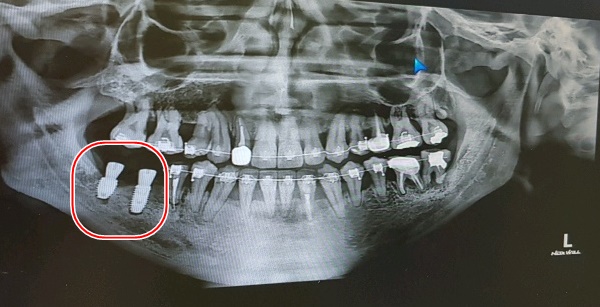

거즈를 물라고 하고 수술이 잘 됐는지 확인차 엑스레이 한번 찍고

다시 또 작업하고, 또 엑스레이 실로 가고를 1번 반복 후 이제 거의다 됐다면서

그렇게 오른쪽 임플란트 작업은 드디어 끝!!

어금니쪽이라 임플란트를 좀 큰 걸로 한건지는 모르겠으나 왜이리 커보이는지;;

그렇게 12일이 지난 후 원래 다니던 교정치과로 갔고, 유지장치 본뜨는 작업을 했다.

20일이 지난 지금은 어느정도 살도 올라오고 통증도 없고 혀로 대도 안아프다.